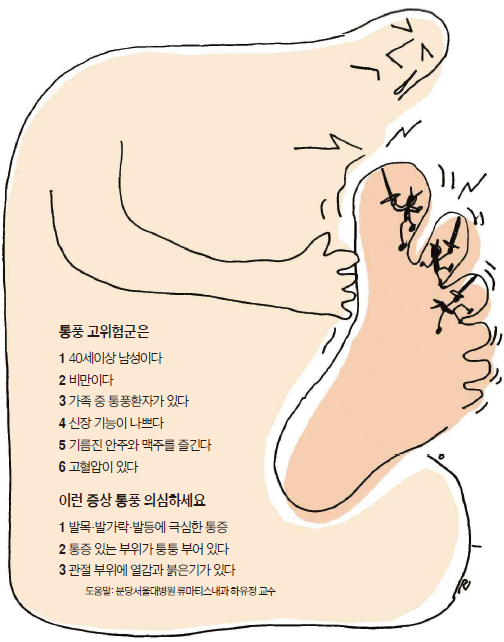

통풍 환자에서는 혈액 내 요산이 지나치게 많아서 이것이 결정체로 변하고,

이 요산 결정체가 관절 내에 침착하여 염증을 유발하게 되는 것입니다.

통풍 관절염은 고요산혈증이 심할수록, 또 기간이 오래될수록 발병할 가능성이 높아집니다.

통풍 환자는 거의 남자이고 대개 첫 발작적 관절염을 40~50세에서 경험합니다.

1) 주로 엄지발가락, 발목, 무릎 등 한군데 관절이 갑자기 빨갛게 부어오르고

2) 통풍이 심하면 발열과 오한을 동반합니다.

3) 처음 발생하는 경우에는 대개 수일 지나면 저절로 소실되어 완전히 회복하고

4) 가장 특징적으로는 엄지발가락 관절에 잘 발생하며

5) 얇은 이불이 스쳐도 아파서 대개 환자들은 양말도 신지 못하고 걸음을 제대로 걷지 못합니다.

6) 통증이 특히 밤에 심해져 잠을 못 이룰 정도에 이르기도 합니다.